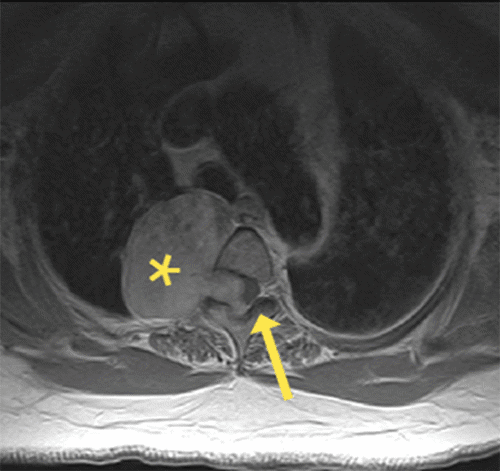

Figure 3. MRI Obtained After First Stage of Resection. Published with Permission

Axial T2-weighted image after the first stage of resection shows relief of mass effect on the spinal cord (arrow).

The surgical plan was complete resection of the mass in two stages. Neurosurgery planned initial surgery as a laminectomy at T2 for debulking and resection of the intraspinal component to decompress the spinal cord and remove the tumor through the foramen. Resection of the intraspinal portion of the mass resulted in resolution of the mass effect upon the spinal cord with partial relief of symptoms. After the first stage of resection, a repeat MRI showed residual components of the mass extending out of the right neural foramen of T2 into the right hemithorax but significant decompression of the spinal cord (Figure 3). Pathology of the spinal tumor specimen from the first stage of surgery was classified as a neurofibroma. Histology confirmed spindle cells arranged in fascicles and bundles with background collagen stroma; no features of schwannoma were seen (no peripheral palisading, Antoni A or B areas).